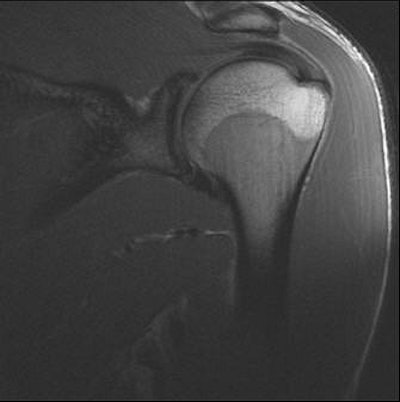

| Images from a prior Combine event. Player with right shoulder pain. Oblique sagittal fat-saturated T2 MR images of the right and left shoulders. Increased signal in the right infraspinatus muscle suggests denervation edema, possibly caused by mass effect from markedly hypertrophied supraspinatus muscle causing pressure on the adjacent suprascapular nerve. |